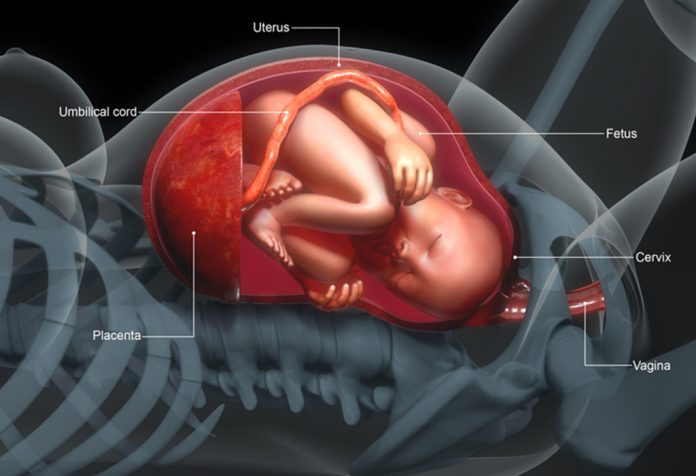

ما هي المشيمة؟

تسمى المشيمة باللغة الإنجليزية باسم (Placenta)، وهي عضو مؤقت يتكون داخل الرحم أثناء الحمل، وهو الرابط بين الأم والجنين خلال تلك الفترة، إذ تلعب المشيمة دورًا حيويًا في تغذية الجنين وتزويده بالأكسجين، بالإضافة إلى إزالة الفضلات.

تتضمن وظائف المشيمة على النقاط التالية:

- تبادل الغازات، إذ تقوم المشيمة بنقل الأكسجين من دم الأم إلى دم الجنين، والعكس صحيح بالنسبة لثاني أكسيد الكربون.

- تمرير العناصر الغذائية الأساسية مثل الجلوكوز، والفيتامينات، والأحماض الأمينية إلى الجنين.

- إزالة الفضلات.

- انتاج الهرمونات للحفاظ على صحة الحمل، ودعم نمو الجنين.

- تساعد على حماية الجنين من بعض المواد الضارة المتواجدة في جسم الأم مثل البكتيريا أو الجراثيم.

تشير حالة ضعف المشيمة عند الحامل إلى عدم قدرتها على القيام بوظائفها بشكلٍ فعَّال، مما قد يؤثر سلبًا على نمو الجنين وصحته.